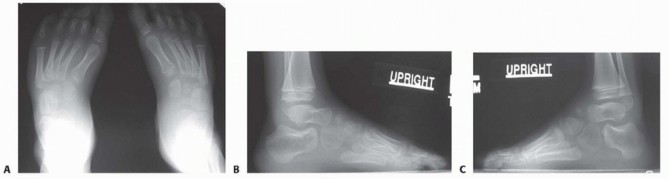

to the lateral border of the foot and a shortened first ray. These findings are consistent with severe or atypical clubfeet (often termed complex clubfoot ) that have a propensity for residual deformity. Illustration 7 for Why Anterior Tibialis Muscle Transfer Fixes Clubfoot --- Illustration 8 for Why Anterior Tibialis Muscle Transfer Fixes Clubfoot ### FIG 5 • Examination findings of residual supination and equinus deformity. A. Forefoot supination. B. Hindfoot equinus. C. Anterior view combined forefoot supination and hindfoot equinovarus. D. Posterior view combined forefoot supination and hindfoot equinovarus. In maximum pronation or maximum supination, the navicular-medial malleolar distance is decreased compared to the normal foot. In fact, the medial malleolus can be difficult to delineate because it is in contact with the navicular. The navicular malleolar distance demonstrates the extent of medial subluxation.It is important to examine gait when possible.During examination of gait, the clinician should identify whether the tibialis anterior is a dynamic supinator; this is best observed in swing phase when no antagonist muscles contract.This finding will confirm the appropriateness of surgery.The strength of the tibialis anterior is tested. With dynamic supination deformity, the supinator action of the anterior tibialis muscle will overpower the dorsiflexor action, thus demonstrating the appropriateness of surgery. In addition, good power is needed for a successful transfer.The clinician should evaluate for other deformities, such as equinus, cavus, varus, adductus, and tibial torsion.Range of motion of the ankle is examined. Transfer will work only as long as there is no fixed contracture of the ankle or heel cord. ## IMAGING AND OTHER DIAGNOSTIC STUDIES Anteroposterior (AP) and lateral radiographs may be helpful to study and quantify various deformities.AP radiographs will demonstrate medial deviation of the metatarsals, which can indicate residual medial displacement of navicular, which is yet to ossify ( FIG 6).On an AP radiograph of normal feet, the line drawn through the long axis of the talus should point to the first metatarsal, whereas the line drawn through the long axis of the calcaneus should point toward the fourth metatarsal.In clubfeet, these lines become more parallel, depicting “stacking” of the talus and calcaneus.Forced maximum dorsiflexion lateral radiographs may reveal hindfoot equinus with midfoot breech.Stacking of the metatarsals on the lateral radiograph identifies the presence of residual forefoot supination (a decreased talocalcaneal angle).Ultrasound evaluation of the foot is not done routinely. However, experimental studies have demonstrated that this technique is capable of documenting the location of the navicular in relationship to the head of the talus. The navicular is subluxated plantarward and medially on the head of the talus.Similarly, MRI can be performed to completely identify the relationships of the cartilaginous bones and the size and presence of the lateral leg muscles.This technology is rarely clinically used, as orthopaedists are aware of the classic deformities that are associated with recurrence and the increased risk of general anesthesia for a childhood MRI scan may not be justified. ## DIFFERENTIAL DIAGNOSIS Residual deformities in clubfoot may be due to unrecognized tarsal coalitions or other conditions in syndromic clubfoot, severe, or complex clubfeet.Unexpected and rapid recurrent deformity in children with previously corrected feet and with known myelomeningocele may be a result of continued neurologic involvement, such as tethering of the spinal cord.

FIG 6 • Weight-bearing AP and lateral radiographs of feet shown in FIG 5. A. The long axes of the talus and calcaneus are somewhat parallel rather than divergent. The metatarsals appear adducted in relation to the talus. B,C. The long axis of the talus and calcaneus appear somewhat parallel rather than divergent on Illustration 9 for Why Anterior Tibialis Muscle Transfer Fixes Clubfoot --- the lateral view of the right foot. The axes of the talus and the first metatarsal do not form a straight line, as opposed to a normal foot. This degree of divergence from this linear alignment represents intrinsic deformity of the clubfoot. The metatarsals are stacked on the weight-bearing lateral views. ## NONOPERATIVE MANAGEMENT Treatment of residual deformity depends on the location, severity, and age of the child.Recasting and repeat tenotomy may be considered in children younger than 18 months of age who have residual deformity.Most residual deformities at this age can be treated by manipulation, followed by application of a toe-to-groin plaster cast with the feet in a fully corrected position for 2 weeks. Most of these patients have residual equinus that requires progressive dorsiflexion at each casting session.After 2 weeks, the casts are removed and reapplied.Usually, three casting sessions are required, for a total of 6 weeks.Thereafter, abduction bracing is reinstituted. Several different abduction orthosis are commercially available and if one system is not well accepted, another maybe better tolerated.In larger children, ankle-foot orthoses (AFOs) may also be used to prevent recurrence.Physiotherapy may also be used in patients with residual deformity. The therapist must be familiar with techniques to manipulate residual forefoot adductus and stretch the posterior contracture without producing or accentuating midfoot breech. In older children and in patients with midfoot breech, it can be difficult to effectively stretch any hindfoot equinus contracture.With residual equinus contracture, abduction bracing is difficult.Unbraceable posterior contracture can then lead to recurrent metatarsus adduction and forefoot supination. Thus, a repeat percutaneous heel cord tenotomy and casting may be required. ## SURGICAL MANAGEMENT In children more than 2 to 3 years of age, and who failed conservative measures to correct deformity, it may be preferable to correct any residual deformity using soft tissue lengthenings or transfers with or without bony procedures.As the anterior tibialis acts as a supinator, lateral transfer of the anterior tibialis tendon is often necessary to correct dynamic supination deformity.The optimal age for lateral transfer of the anterior tibialis tendon varies from case to case. Important factors are the rapidity of recurrence, the strength of the anterior tibialis muscle, the presence of fixed forefoot deformity, or the presence of concurrent equinus deformity or cavus and the desired location to transfer the tendon.Ponseti advocated transferring the tendon completely into the lateral cuneiform as such the surgery should be performed after the lateral cuneiform ossification center appears (2 to 4 years of age). Although some surgeons have successfully transferred tendons into cartilage anlage, this chapter outlines transfer of the tendon into the ossified cuneiform.Alternatively, some surgeons have advocated transfer of the anterior tibialis tendon into the peroneus tertius, half of the peroneus brevis, or occasionally into metatarsals. In general, insertion of the tendon along an axis drawn along the third metatarsal will promote foot dorsiflexion.The split anterior tibialis tendon transfer (SPLATT) of Hoffer et al 6 is rarely used in idiopathic clubfeet but is an excellent method for correcting dynamic supination deformity as a result of spasticity associated with disorders such as cerebral palsy. This method may have some use in children with mild, flexible forefoot supination who require surgery for other deformity. ## Preoperative Planning for Transfer into the Lateral Cuneiform Feet with residual deformity should be extensively evaluated by clinical and radiographic assessment before surgical planning. Each foot should be treated individually, as no single treatment plan is appropriate for all feet.Associated deformities must be identified. For example, an anterior tibialis transfer will function poorly in the face of a fixed equinus contracture. In this case, it will be necessary to correct equinus deformity with a heel cord tenotomy or lengthening or posterior release.Residual varus deformity may indicate the need for an opening wedge or sliding calcaneal osteotomy.Persistent metatarsus adductus may necessitate midfoot osteotomies in order for the lateral border of the foot to be reduced.